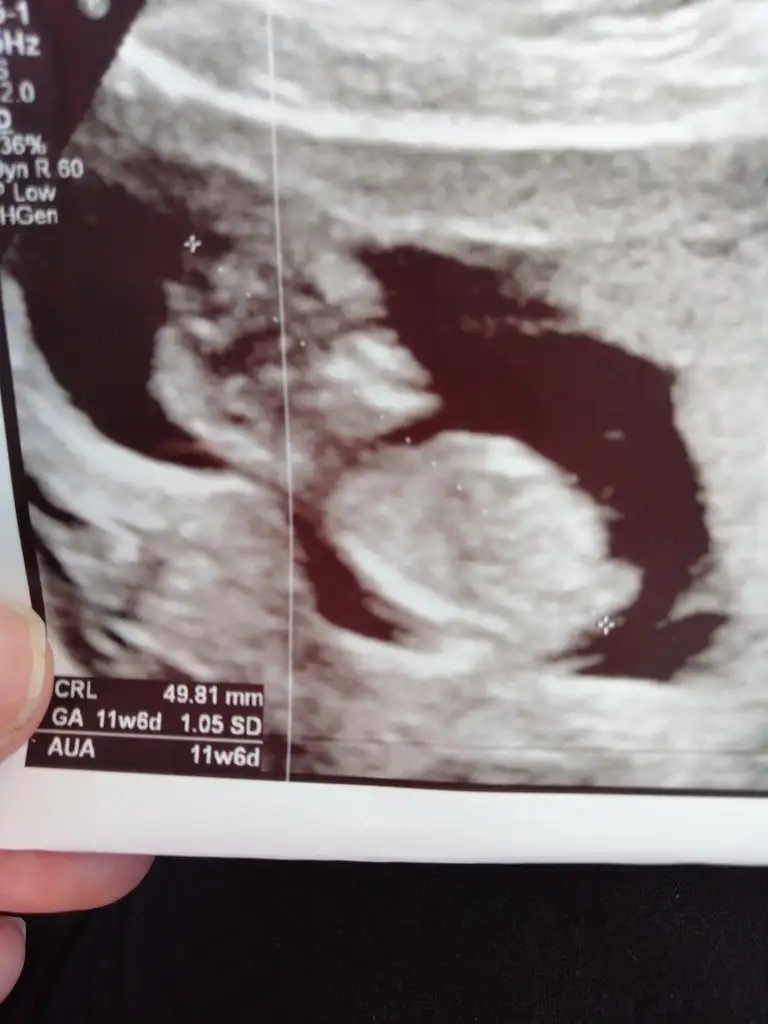

Hanımlar benim çocuğuma da tahminlerinizi rica ederim meraklıyız biz biraz da 🙈(10+6 usg) Şimdiden çok teşekkür ederim 💛

Eklentiler

• B77FF683-9DAA-4B25-AE8E-C58C8240B115.webp

B77FF683-9DAA-4B25-AE8E-C58C8240B115.webp

24,7 KB · Görüntüleme: 86